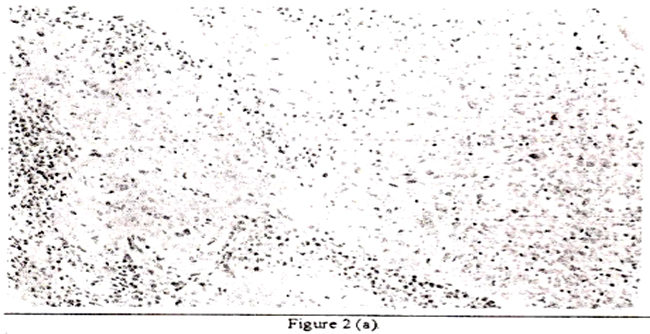

and p53 by immunohistochemistzy (Table II. Figure 2 and 3).

The high risk HPVs were found in 36 (88%) of 41 cervical 5 (33%) of 15 endometrial and none of ovarian (n3) and rectal (n= 1 ) carer omas I IPV 33 was predominant both in cervical (28 cases) and endometrial careinomas (5 cases). HPV 18 was found in 19 cervical and 2 endometrial carcinomas, while HPV 16 was found only in 14 cervical carcinomas. Single HPV infection was detected in 16 cervical arid 3 endometrial carcinomas. On the other hand, 20 cervical and 2 endometrial carcinomas harboured more than two types of HP V. p53 over-expression was found in 28 (68%) of 41 cervical carcinomas and 7 (47%) of 15 endometrial carcino mas, 2 (66%) of 3 ovarian carcinomas and one rectal carcinoma. Fourteen cervical and 6 endometrial carcinomas found positive for p53 alteration contained more than 10% of cells stained strongly with CM-1 polyclonal antibody. The correlation between presence or absence of HPV and p53 mutation detected by irnmunohistochemistiy is shown in Table III.